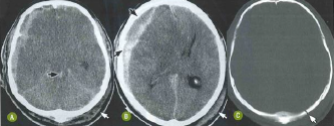

Paciente de 26 anos foi vítima de acidente automobilístico com traumatismo cranioencefálico. Nas imagens tomográficas a seguir, pode-se observar

Provas